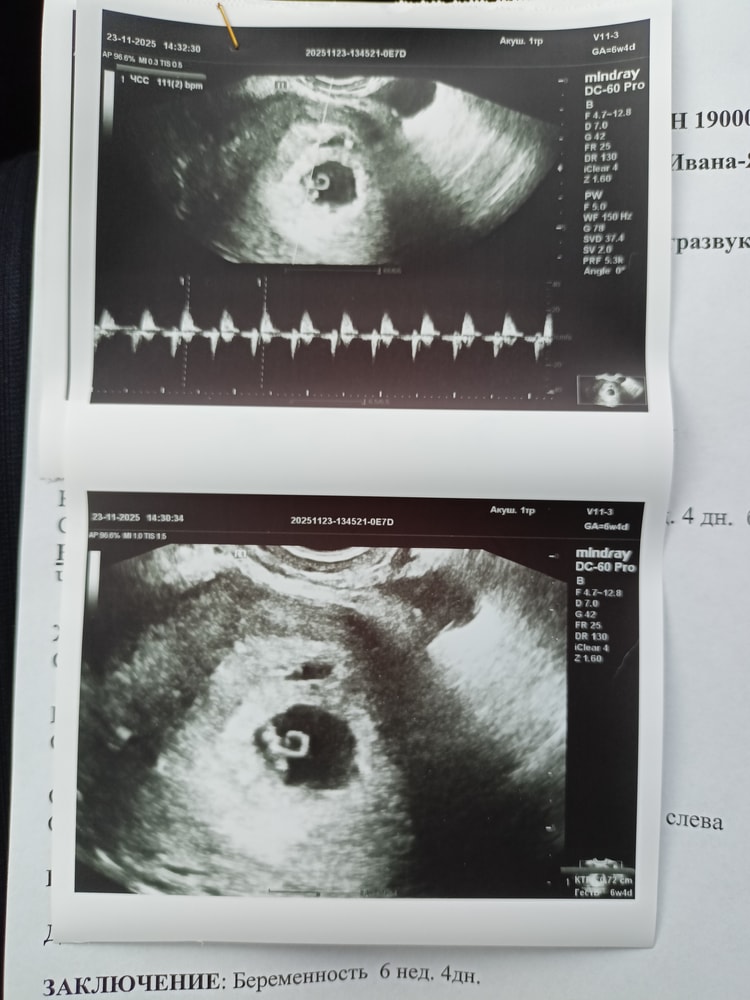

Токсикоз пришел в 5,6 в виде монотонной тошноты, мутит, не критично, спасибо без рвоты,но тем не менее,не приятно,так скажем. Помогает покушать, но эффекта хватает буквально на 10-15 мин. Помогает свежий воздух,на улице в разы легче ,в связи с этим балкон дома открыт практически кругл